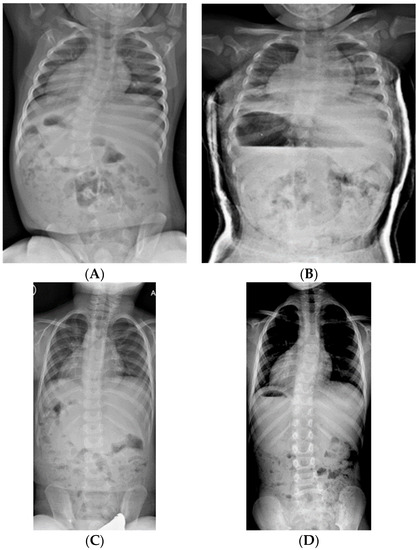

Figure 5.

(A) 10-year-old female with PWS deletion type and 41° curve. (B) Standing in her daytime thoracic-lumbar-sacral orthosis (TLSO). (C) Supine in her nighttime Providence brace. (D) At 13 years, with curve improved to 25°.